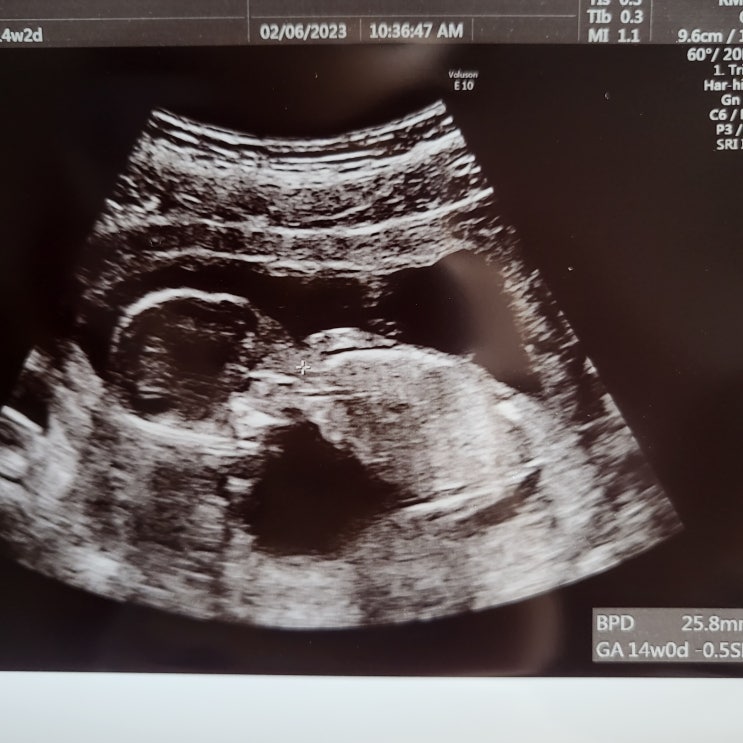

[임신 중기] 16주 2차 기형아 검사/ 뇌 물혹(맥락막총낭종) / 증상/ 태동/ 20주 정밀검사/ 임산부 필라테스

[임신 중기] 16주 2차 기형아 검사/ 뇌 물혹(맥락막총낭종)/ 증상/ 태동/ 20주 정밀검사 안녕하세요 졔월드...

[임신 초기] 임신 12주 기형아 검사 NIPT/ 일본 보건소 임신 등록/ 베이비 용품 (에르메스/ 디올/ 버버리)

[임신 초기] 임신 12주 기형아 검사 NIPT/ 일본 보건소 임신 등록/ 에르메스 베이비 용품 안녕하세요 ...